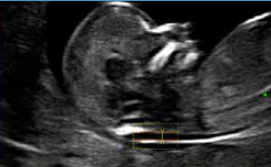

Auto IT – Automatic measurement of Intracranial Translucency (IT)